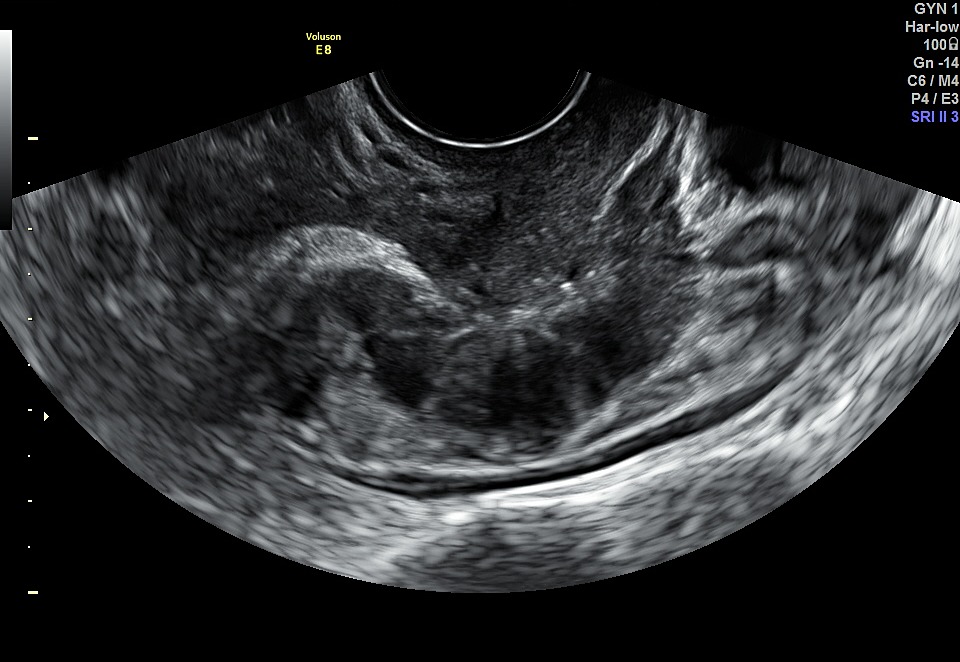

3

Ultrasound image showing asymmetry between the anterior and posterior myometrium and an irregular junctional zone. This is indicative of moderately diffuse adenomyosis, Type 1–2.